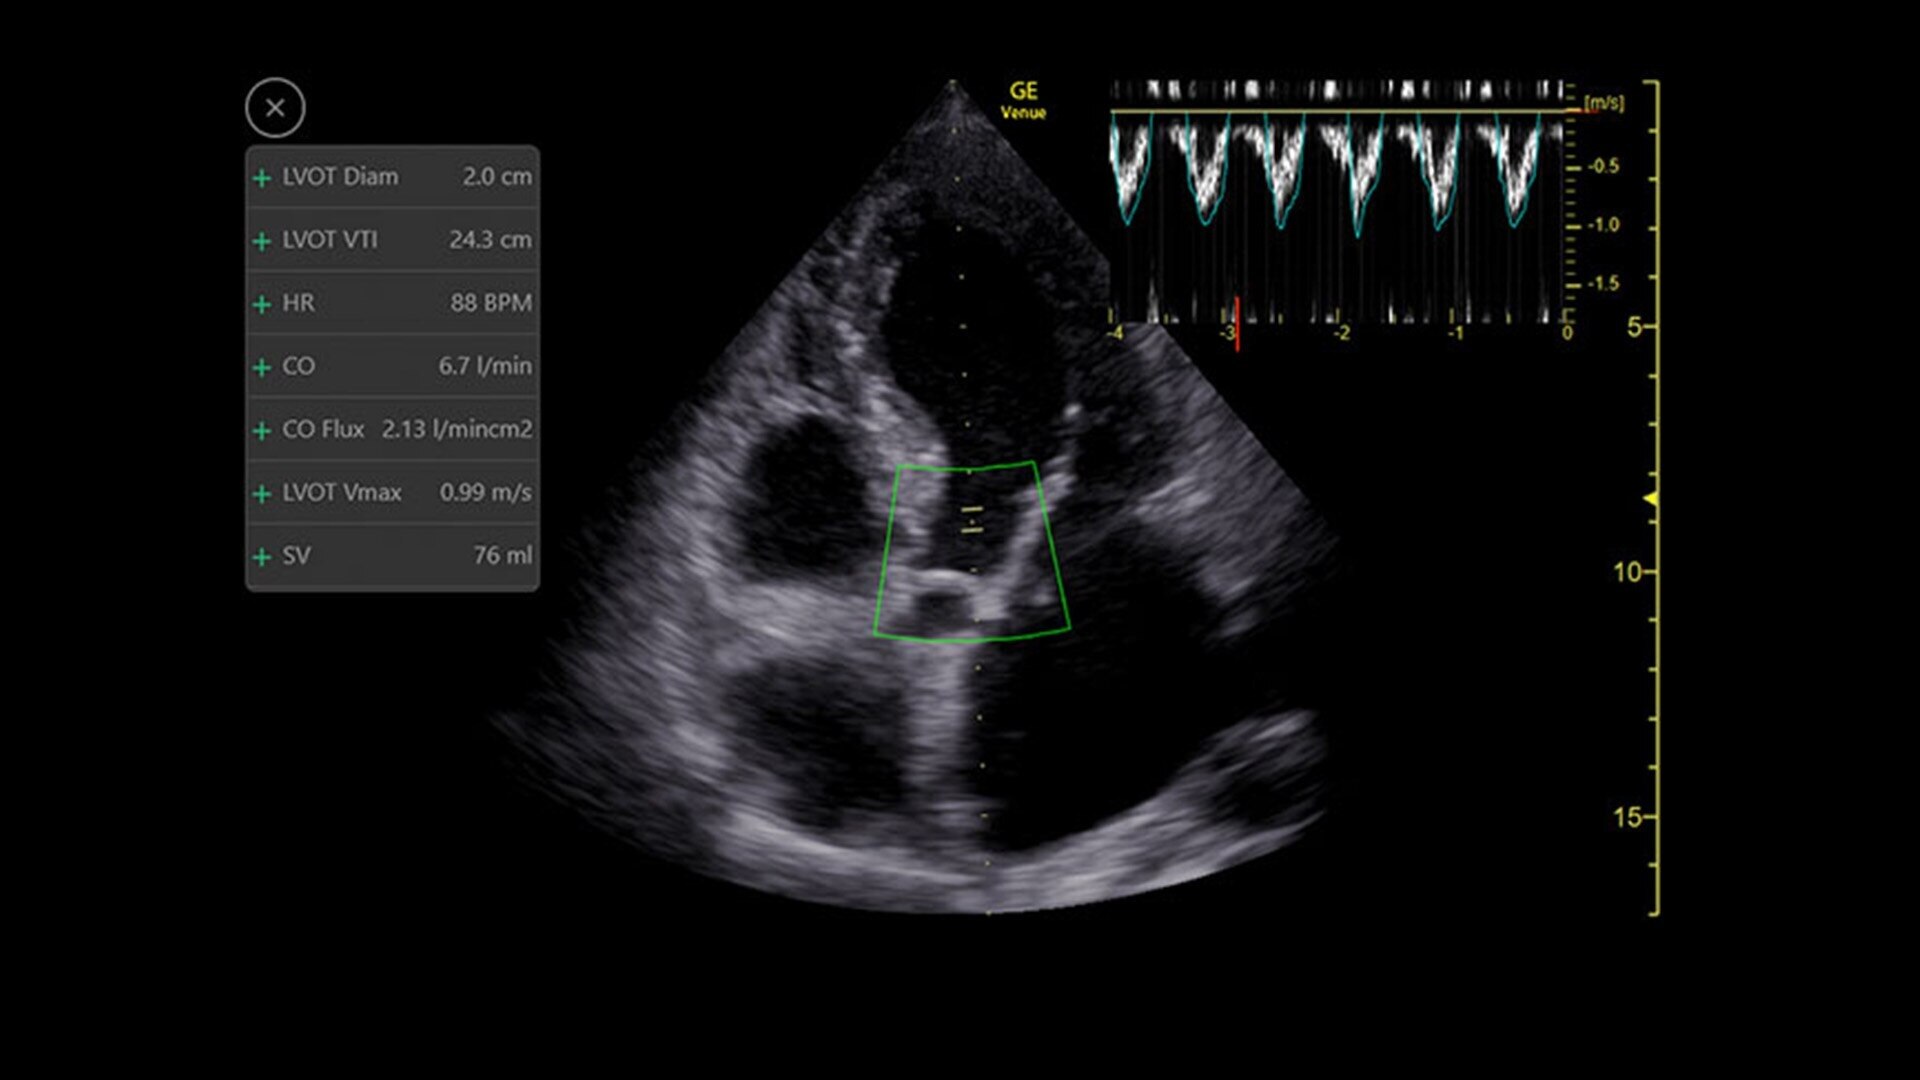

Shock Toolkit

Automated shock assessment

Medical shock in its many forms is a leading cause of death around the world.1 While ultrasound can help identify the cause of shock, it can require many manual steps and the guidelines can be complex. The Shock Toolkit quickly gets you the information you need to make fast decisions when triaging patients in shock. With tools such as Auto B-Lines, Auto VTI and Auto IVC, it simplifies a complicated process by utilizing automated calculations that focus on key indicators of patient status; the heart, lungs and inferior vena cava.